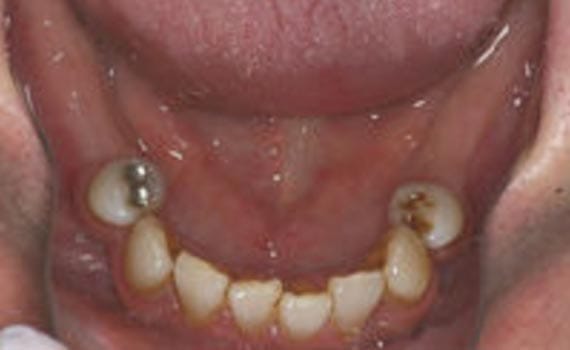

Surgical Templates: Implant Guide Basics 3D Imaging For Treatment Planning & Precise Implant Placement Virtual 3D Treatment Planning Derived CAD/CAM Drilling Guide Jawbone Refortification: Titanium Implants & Titanium Bridge #1 3D Treatment Planning For Full Mouth Teeth Replacement All Teeth Lost to Disease & Normal Wear & Tear Implant Placements In Healthiest Bone Creates Strongest Bite Jawbone Refortification: Titanium Implants & Titanium Bridge #2 Embedded Titanium Implant Frame For Severe Bone Loss Bone Too Thin For Implants Embeddable Implant Frame X-Ray Confirmation Of Embedded Frame Snap-On Cosmetic Denture Single Implant Molar Tooth Replacement Best Solution For Long Term Endurance (avoiding bridgework) Adding Bone for Simple One Tooth Replacement Avoiding Invasiveness of 3 Unit Bridge (no anchor teeth grinding) Before After Popular Choice for Molar Tooth Replacement Expected Extreme Bite Pressure Maintains Optimal Bone Health Avoiding Bone Loss That Commonly Occurs Under A 3 Unit Bridge Before After Molar Teeth Replacement via Guided Implant Surgery CT Scan Based Diagnostics Assures Rock Solid Placement – Balance Excessive Decay & Gum Disease Total Diseased Tissue Removal Surgical Guide Alignment New Molar Bite Health Tooth “Creation” for Congenitally Missing Canines Baby Teeth – Yes | Adult Secondaries – No Special Tissue Punch Eliminates Need For Gum Surgery Minimal Need For Grafting Products Precision Implant Alignment Check Final Abutment Prep Perfect Match For Mother Nature 3 Unit Bridge With Implant Anchors => Maximum Bite Strength Avoiding Failures Caused by Modifying Adjacent Teeth for Anchoring Maintain Bone – Adjacent Tooth Health Before After Get Started Today Request Appointment Meet the Doctor Watch Our Video